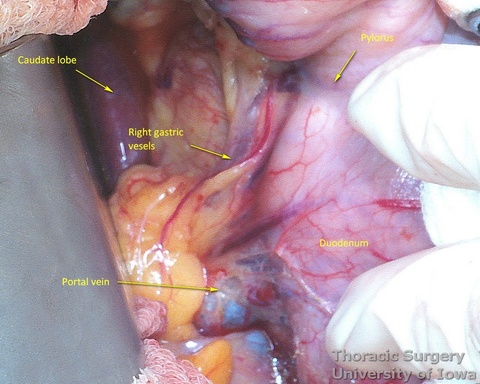

- The right gastric artery is preserved

- Once the stomach is mobilized and reflected anteriorly, the left gastric vascular pedicle is identified and dissected close to the origin for adequate lymphadenectomy. Care is taken to not injure splenic artery and pancreas.

- Postradiation adhesions may be dense.

- Left gastric vessels are divided with an endoscopic linear cutting stapler proximally, including all adjacent lymph nodes in the specimen.